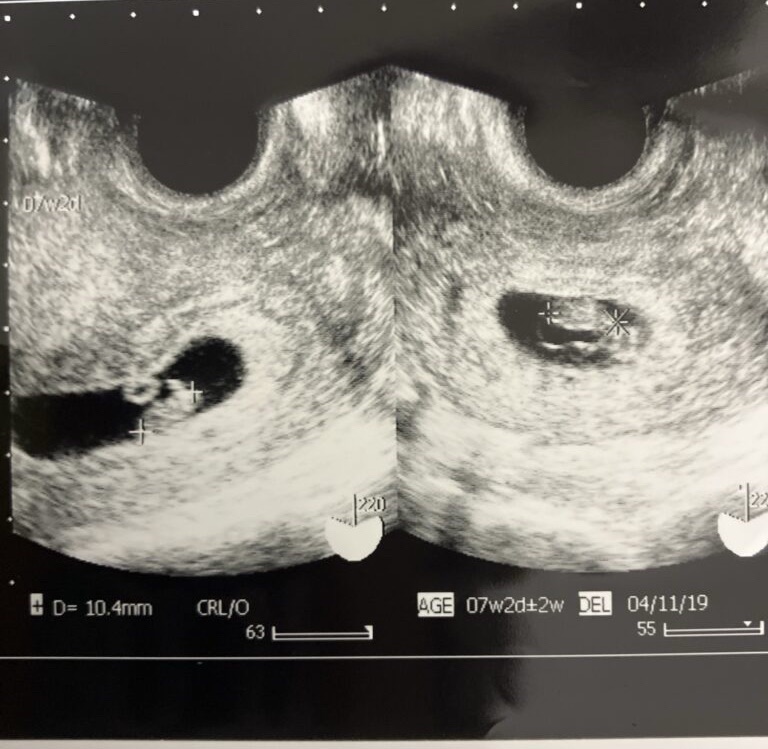

ãããĻč¨ēå¯ããã¨

ãããã§ã¨ãããããžããåĻå¨ ã§ããīŧååã§ããã

ãŖãĻãĩãŠãã¨č¨ãããžããã

ãããŖīŧīŧããŖīŧīŧååīŧīŧååâĻååãâĻīŧã

æŗåŽå¤ãŽäēã§ãããã¯įŦ

å įã¯ãéĸįŊããããŧã¯ããããĒããĻįŦããĒãããåįã§čĒŦæããĻãããžãã

ããģãããããããžããīŧã¤ããããååã ããįĸēįã¯éĢãã¨æããã¨ã

ã¨ãĢããéŠãããŧåãå ĨãããŽãĢæéããããžãããæ§ãã¯ããŖãããŠããžããčĒåãŽåäžãååã ãĒããĻãããäŋĄããããīŧīŧ

å¤Ģã¯ã¨ãĢãã大åãŗã§åŦãããã§ããããį§ã¯ä¸åŽããŖãąããååãŽãã¨ããããããŠãããŖãĻč˛ãĻããããžããŠãããŖãĻįŖãīŧīŧããããĒãäēã ããã§ãåŦãããŽãĢä¸åŽã ããå¨ããĢããžã č¨ããĒããīŧčŊãĄįããĒãæĨã ãĢãĒããžããã